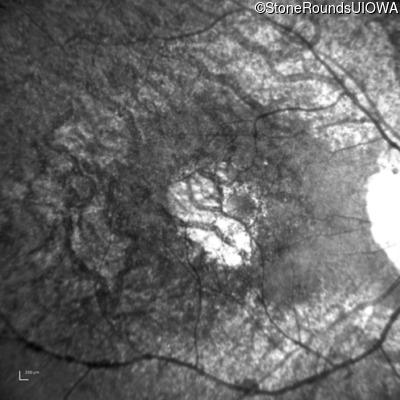

Age at visit: 63 years

OD OS

This 63 year old woman has had normal vision for most of her life, but recently developed difficulty seeing in dim light.

Diagnosis & molecular findings

Disease Gene Allele 1 variant(s) Allele 2 variant(s) Inheritance mode

AD Retinitis Pigmentosa SAG Cys147Phe TGT>TTT   AD